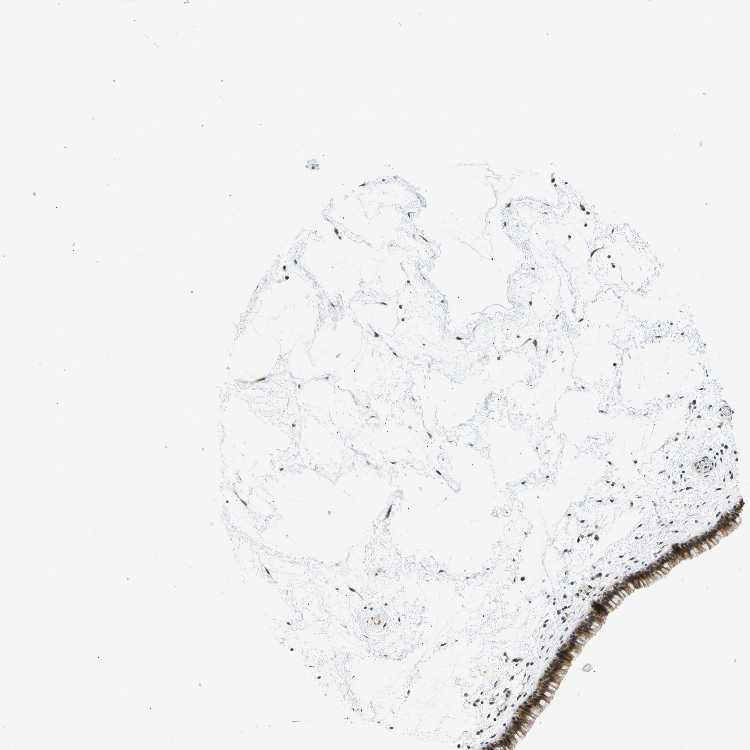

TISSUE PRIMARY DATA NASOPHARYNX Show tissue menu

NASOPHARYNX - Antibody stainingi

Antibody staining in the annotated cell types in the current human tissue is reported as not detected, low, medium, or high, based on conventional immunohistochemistry profiling in selected tissues. This score is based on the combination of the staining intensity and fraction of stained cells.

Each image is clickable and will lead to virtual microscopy that enables deeper exploration of all samples and also displays staining intensity scores, fraction scores and subcellular localization as well as patient and tissue information for each sample.

Antibody CAB012982

Respiratory epithelial cells Medium